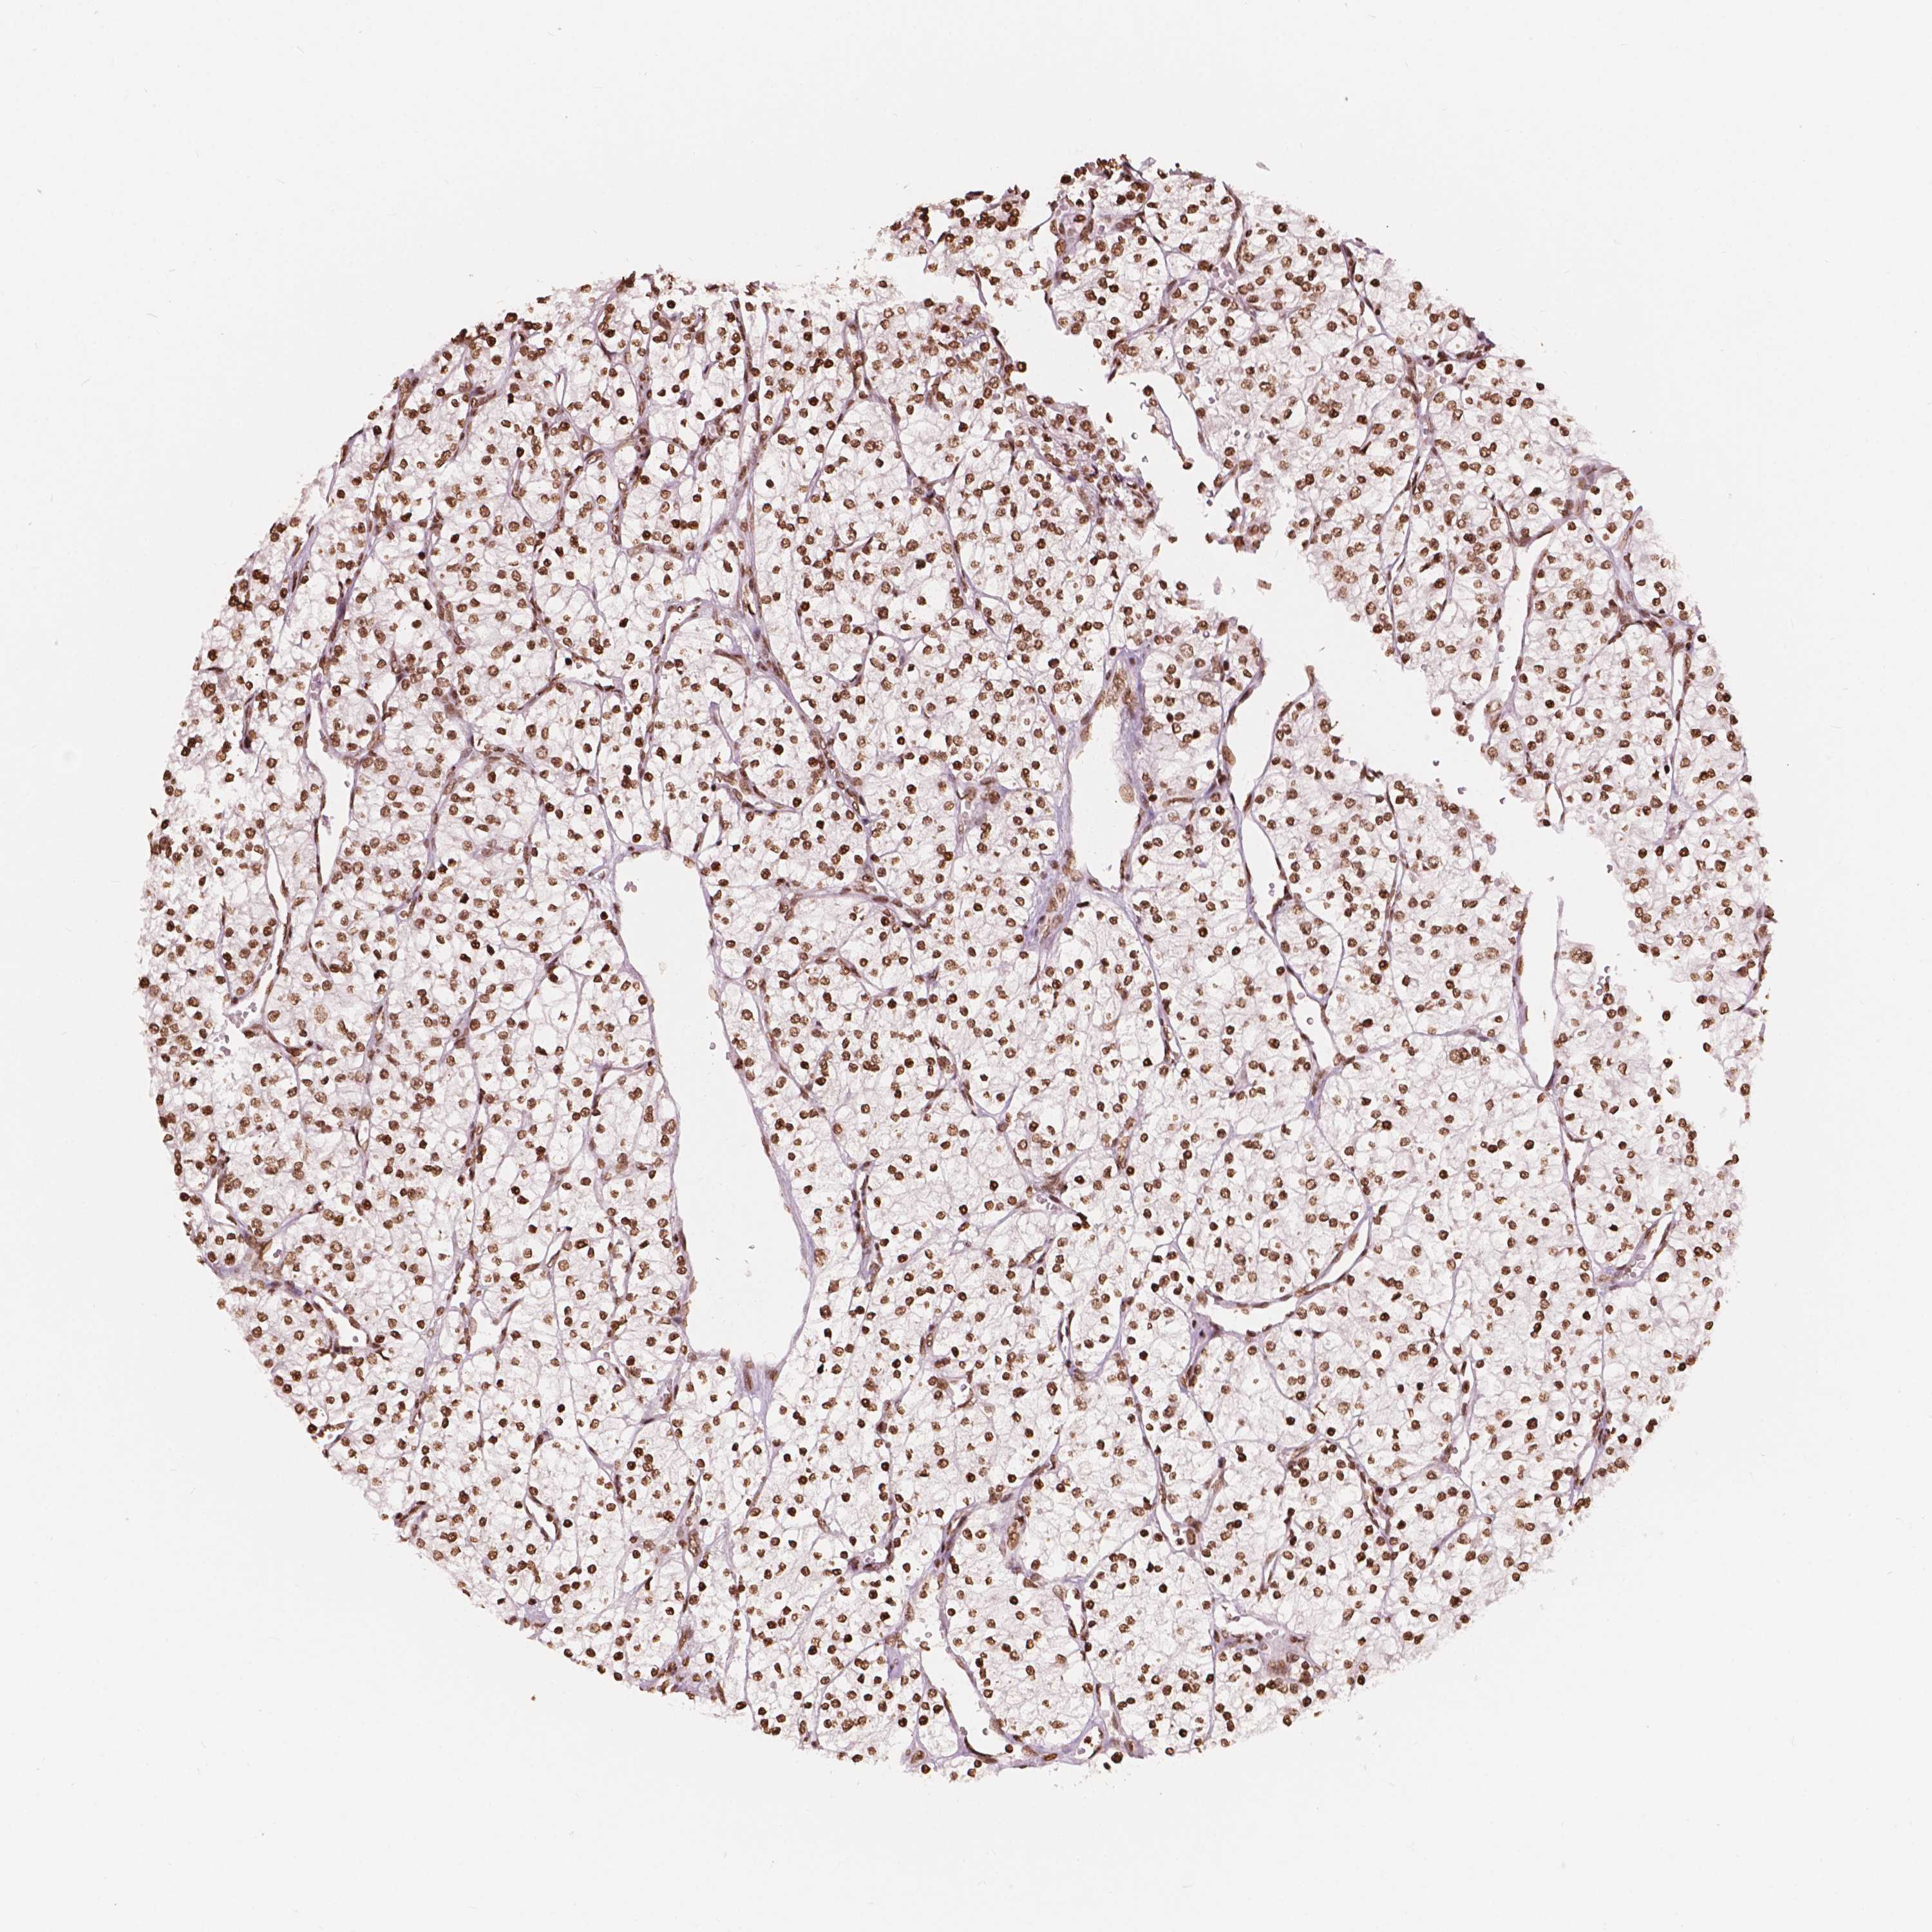

TCGA RNA samplesi

RNA-seq data is reported as average FPKM (number Fragments Per Kilobase of exon per Million reads), generated by the The Cancer Genome Atlas (TCGA) .

Normal distribution across the dataset is visualized with box plots, shown as median and 25th and 75th percentiles. Points are displayed as outliers if they are above or below 1.5 times the interquartile range. FPKM values of the individual samples are presented next to the box plot.

Average pTPM 0.1

Number of samples 100